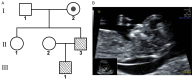

The 3q29 duplication syndrome is an uncommon imbalanced chromosomal disorder with highly variable manifestations, mainly characterized by a mild mental anomaly, eye abnormalities, and developmental delay. Only a few such cases have been reported with significant phenotypic heterogeneity. Here, we reported a case with familial 3q28q29 duplication that was 8.5 Mb in length, covering all fragments from previous reports. A series of genetic detection techniques, including karyotyping, chromosomal microarray, and fluorescence in situ hybridization, demonstrated that the rearrangement, in this case, was due to a three-chromosome translocation of the paternal grandmother of the fetus. Interestingly, only mild intellectual disability in the father and slightly thick nuchal translucency (NT) in the fetus were observed. The fetus was delivered at term and showed normal developmental milestones. Our study increased the understanding of this syndrome and highlighted the necessity and importance of the rational use of multiple genetic techniques in prenatal diagnosis.